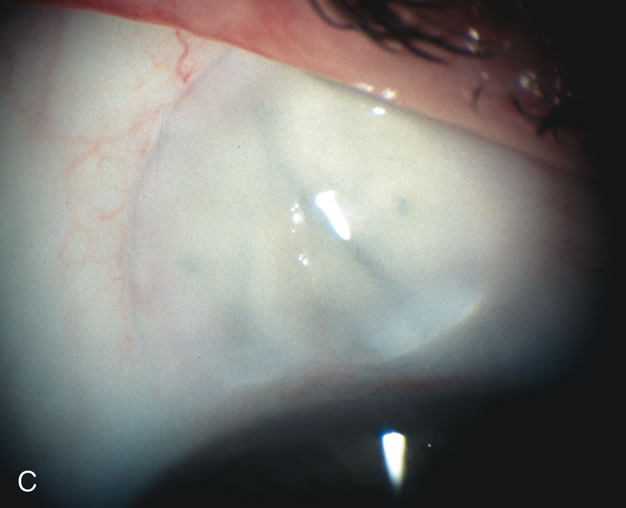

During preoperative slit-lamp biomicroscopy, the surgeon evaluates the condition of the conjunctiva and decides on a fornix-based or a limbus-based conjunctival approach.174–177 There are definite advantages and disadvantages of each approach (Table 3). With proper wound construction, there appears to be very little difference in long-term IOP control between the two incisional groups. However, the long-term bleb appearance varies considerably between the two incisional groups,178 with a limbus-based conjunctival flap more likely to develop a cystic bleb especially if an antimetabolite is used179 (Fig. 8).

Fig. 8. Bleb appearance after limbus-based versus fornix-based conjunctival flaps. Even though the IOP is thought to be equivalent between limbus and fornix-based conjunctival flaps, the final bleb appearance varies considerably. A. During a limbus-based approach, an incision through conjunctiva 10 mm posterior to limbus will sever through multiple arterial vessels, increasing the likelihood of an avascular bleb. B. The tissues are dissected down to the sclera further cutting feeder vessels from Tenon's capsule. C. The wound is closed inciting a cascade of wound healing events that may ultimately lead to scarring producing a barrier to aqueous flow. D. This leads to walling off of a bleb that has lost some of its overlying vascularity (pale cystic avascular bleb). E. During a fornix-based conjunctival approach, the incision is made at the limbus and tissues undermined. F. The incision is closed at the limbus; no conjunctival vessels are severed over the bleb area. G. This fosters the formation of a shallow diffuse pale bleb with a normal vessel pattern.